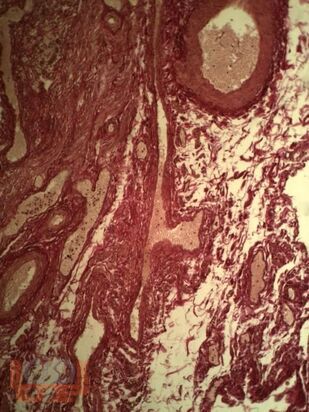

В монографии изложены данные отечественных, зарубежных авторов, результаты собственных исследований, посвященных причинам и механизмам апоплексии яичника у женщин и методам реабилитации для предупреждения рецидива заболевания. Представлены собственные результаты клинико-лабораторных, инструментальных методов исследования, а также опыт применение квантовой терапии в раннем послеоперационном периоде у пациенток с апоплексией яичника.